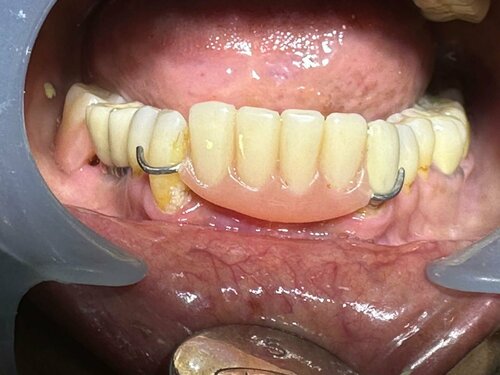

Dr. Gautami Phadke, Consultant Dental Surgeon and Root Canal Specialist in Karve Nagar, Pune, recently helped an elderly patient transition from weari...